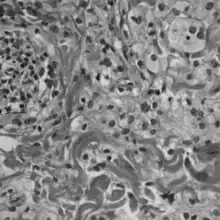

Histologically, ECD differs from Langerhans cell histiocytosis (LCH) in a number of ways. Unlike LCH, ECD does not stain positive for S-100 proteins or Group 1 CD1a glycoproteins, and electron microscopy of cell cytoplasm does not disclose Birbeck granules.[6] Tissue samples show xanthomatous or xanthogranulomatous infiltration by lipid-laden or foamy histiocytes, and are usually surrounded by fibrosis. Bone biopsy is said to offer the greatest likelihood of reaching a diagnosis. It would appear that approximately half these patients harbor point mutations of the BRAF gene at codon 600 substituting the amino acid glutamine for valine. In some, there is histiocyte proliferation, and on staining, the section is CD68+ and CD1a-.